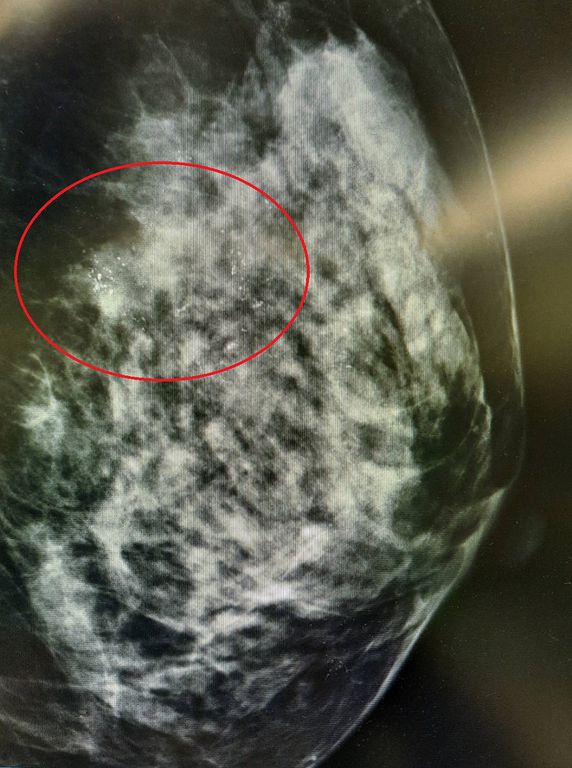

隨著技術的不斷進步,乳癌切除與重建手術已經可以由同一位取得重建專科資格的醫師執行。以53歲的張女士為例,她在半個月前接受乳房攝影檢查,發現右側有瀰漫性微小鈣化點,進一步至台北慈濟醫院求診,經穿刺切片檢查後,病理診斷為乳管原位癌,並無淋巴轉移。一般外科張健輝醫師執行內視鏡乳頭皮瓣保留乳房全切除術並立即進行重建,僅需一次手術即可完成所有治療計畫,術後張女士恢復良好,兩日後平安出院。

乳癌長年位居台灣女性癌症發生率之首,發生率逐年遞增且有年輕化趨勢,但隨著早期篩檢普及,患者通常在「原位癌」階段即被診斷。張健輝醫師指出:「據國健署統計,台灣乳癌患者中有四分之一屬於原位癌,指癌細胞侷限於乳管內,未侵犯周圍組織,惡性度較其他乳癌低,但仍是乳癌進展初期,未及時接受治療,病程可能快速惡化並轉移至身體其他部位,如骨骼、肝臟、肺部及腦部,將大大增加治療的難度,並降低患者的存活率,不可輕忽。」